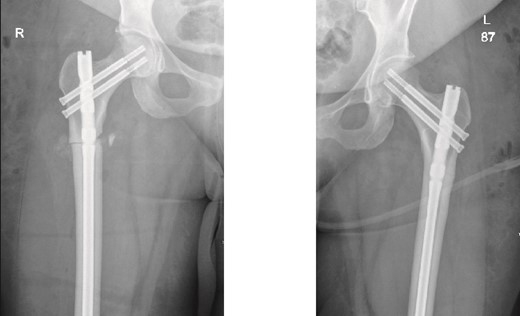

The patient was seen in the clinic at 2 weeks, 6 weeks, and 6 months post-surgery. She was doing well, reporting only mild pain. She was fully weight-bearing with the assistance of a cane and had good range of motion (Figs 3 and 4).

6-weeks follow-up anteroposterior (AP) view of the right and left femurs after CRIF with IM nail.